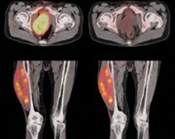

Pruebas de imágen

Las pruebas de diagnóstico por imágenes utilizan ondas sonoras, rayos X, campos magnéticos o sustancias radiactivas para crear imágenes del interior del cuerpo. Las pruebas de diagnóstico por imágenes pueden realizarse por diversos motivos, como:

Las imágenes más representativas o más comunes son:

4. PET scan